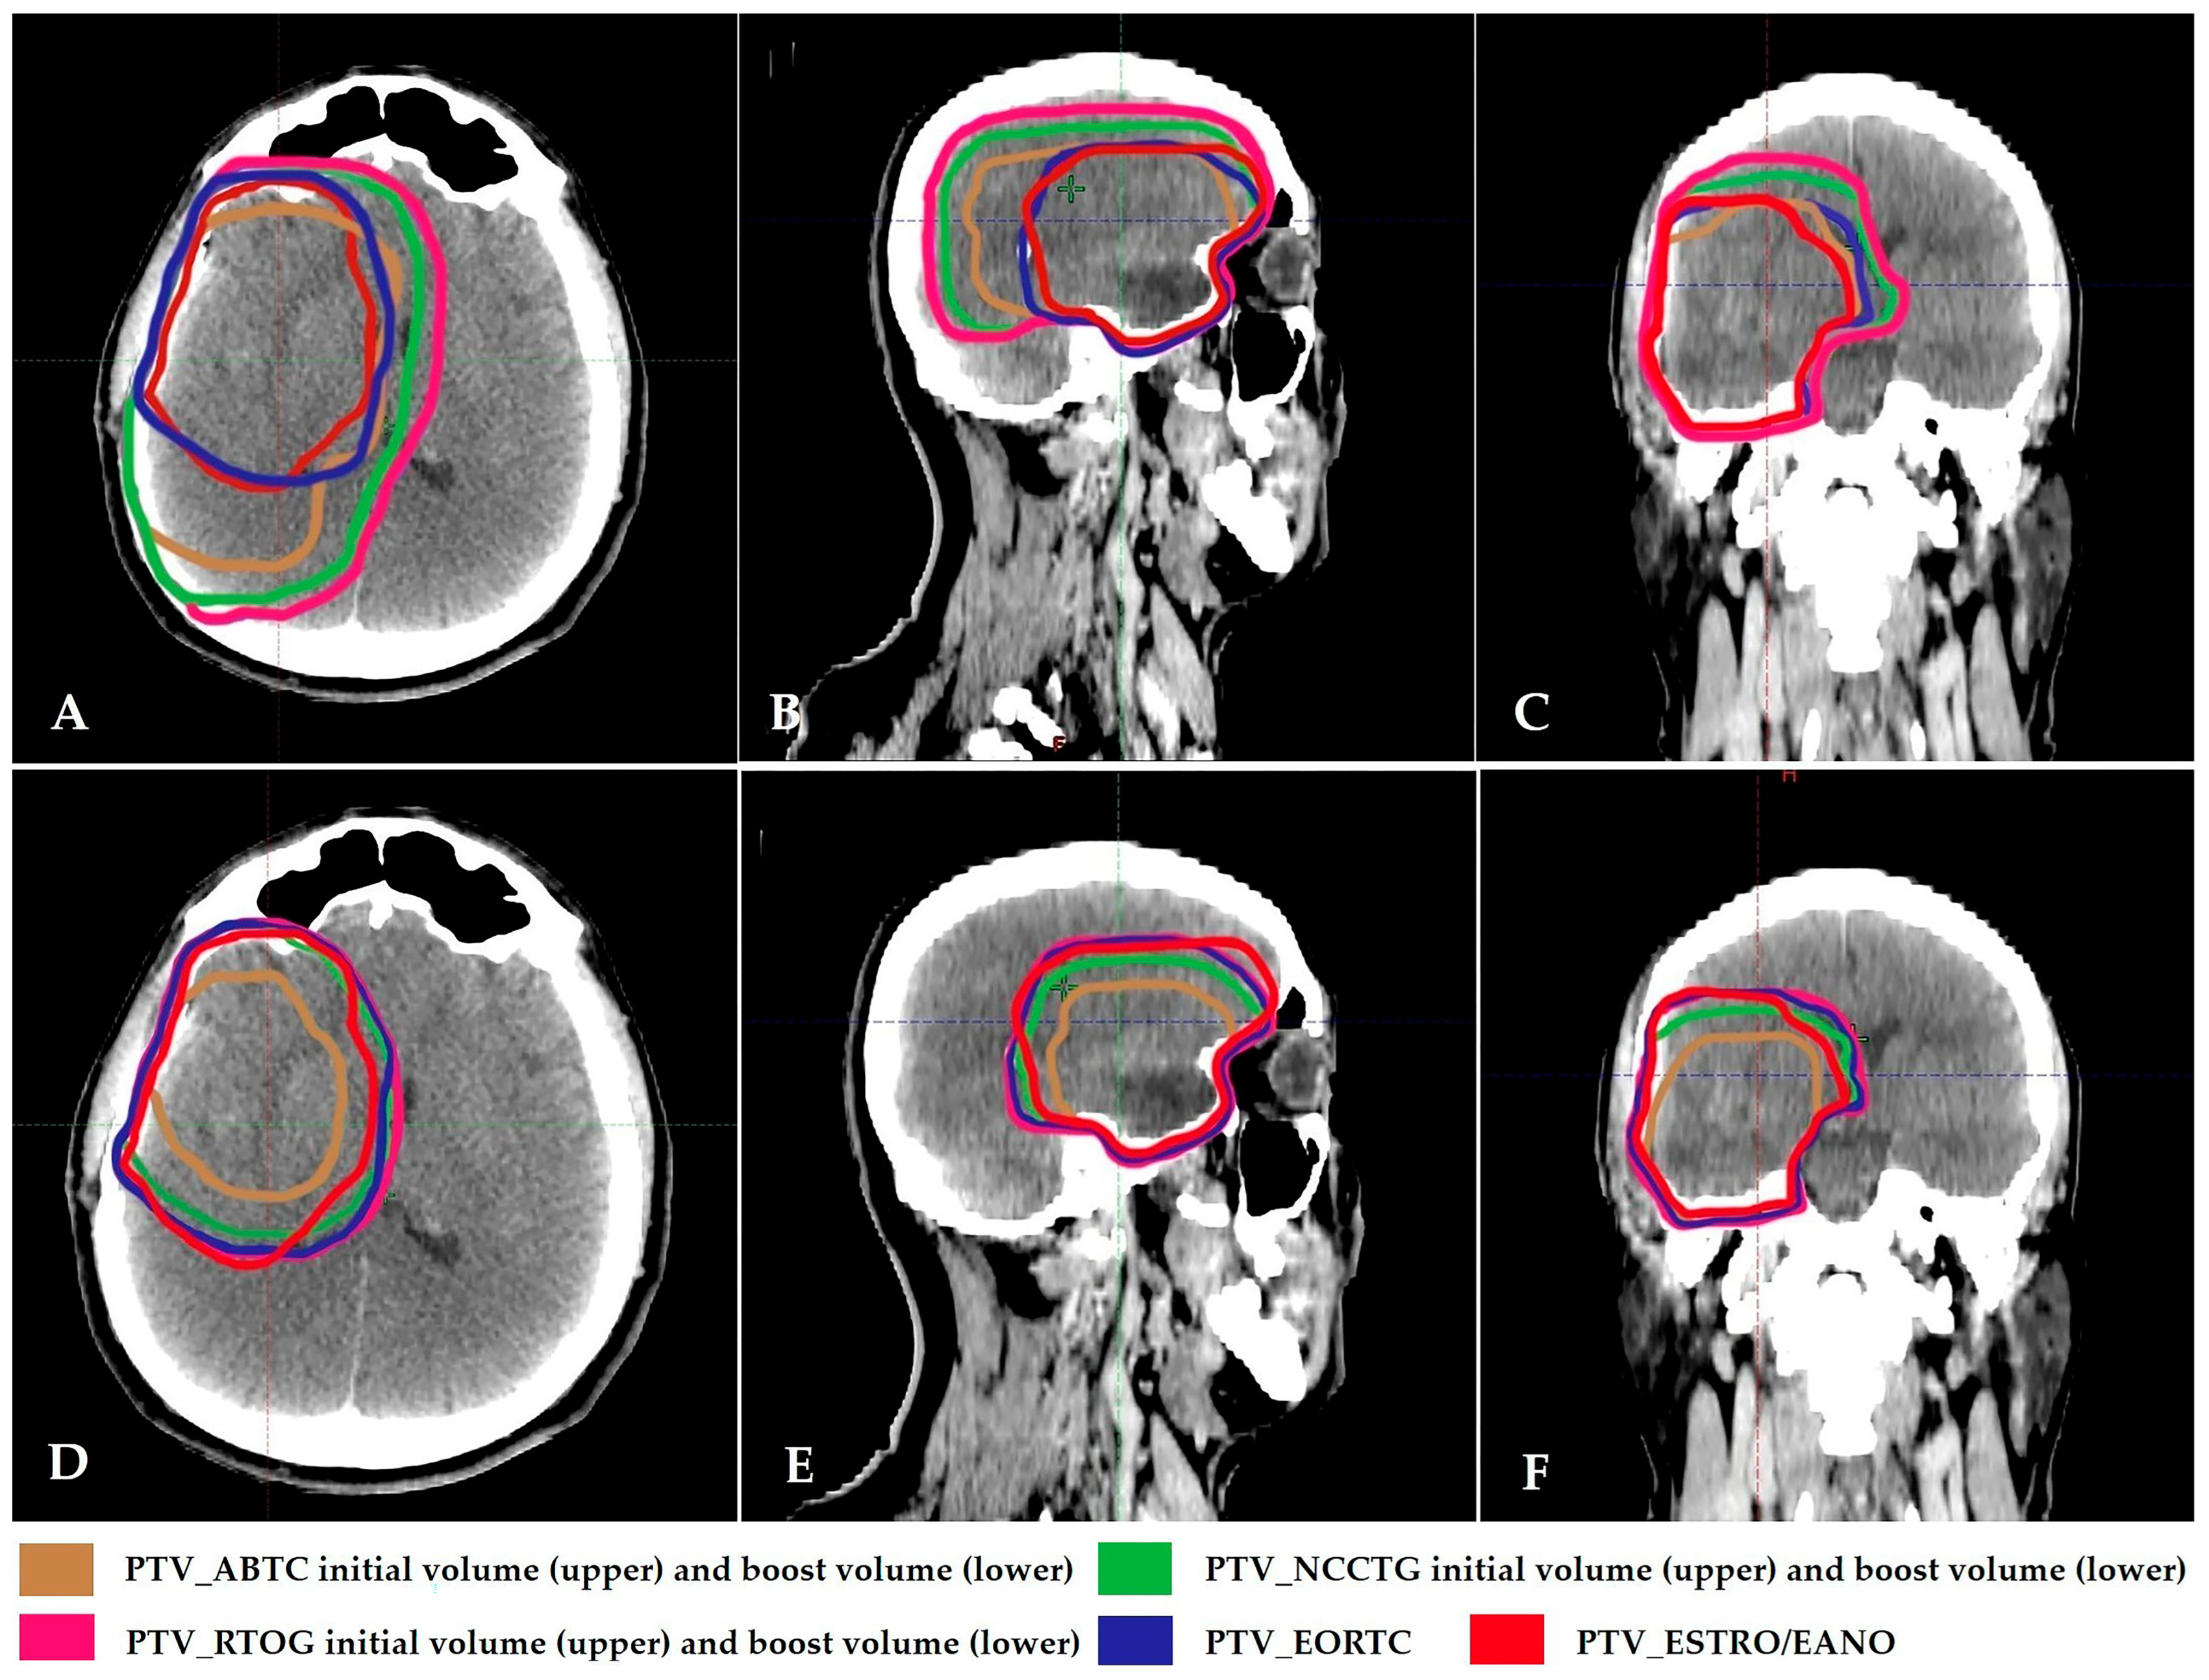

| Group | Definition | CTV-Initial | CTV-Boost | PTV |

|---|---|---|---|---|

| ABTC | Two-phase: 46 + 14 = 60 Gy | T2 + T1E + resection cavity + 5 mm | Resection cavity + T1E + 5 mm | 5 mm |

| EORTC | Single-phase | Resection cavity + T1E + 2 cm | - | 5 mm |

| NCCTG/Alliance | Two-phase: 50 + 10 = 60 Gy | T2 + T1E + resection cavity + 20 mm | Resection cavity + T1E + 20 mm | - |

| RTOG/NRG | Two-phase: 46 + 14 = 60 Gy | T2 +T1E + resection cavity + 20 mm | Resection cavity + T1E + 20 mm | 5 mm |

| ESTRO/EANO | Single-phase | Resection cavity + T1E + 15 mm (include non-contrast-enhancing tumor if suspected on FLAIR imaging) | - | 3 mm |